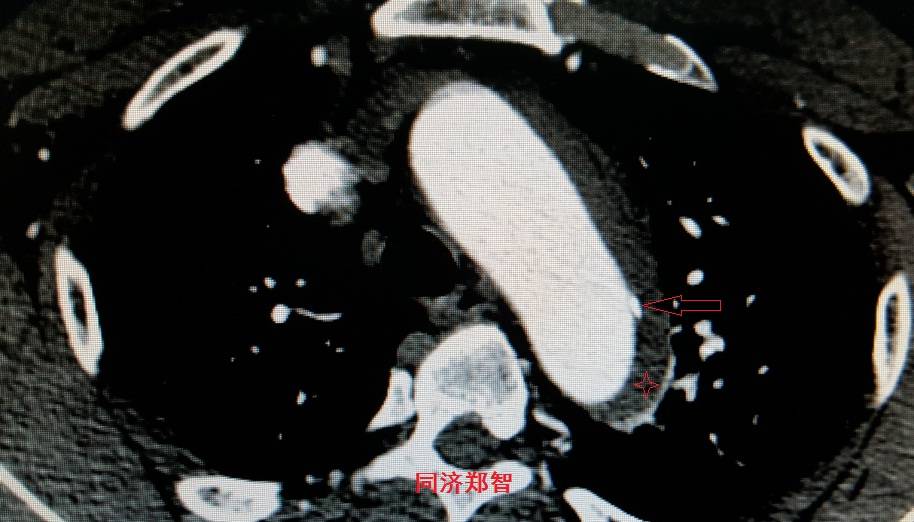

平扫CT提示主动脉弓层面及右肺动脉层面均可见主动脉血管腔内的内膜片影(红色箭头所示),CTA显示为A型主动脉夹层。